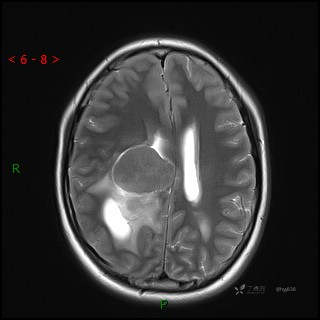

辅助检查:CT MRI

临床诊断:脑室占位

颅脑CT平扫

MRI平扫